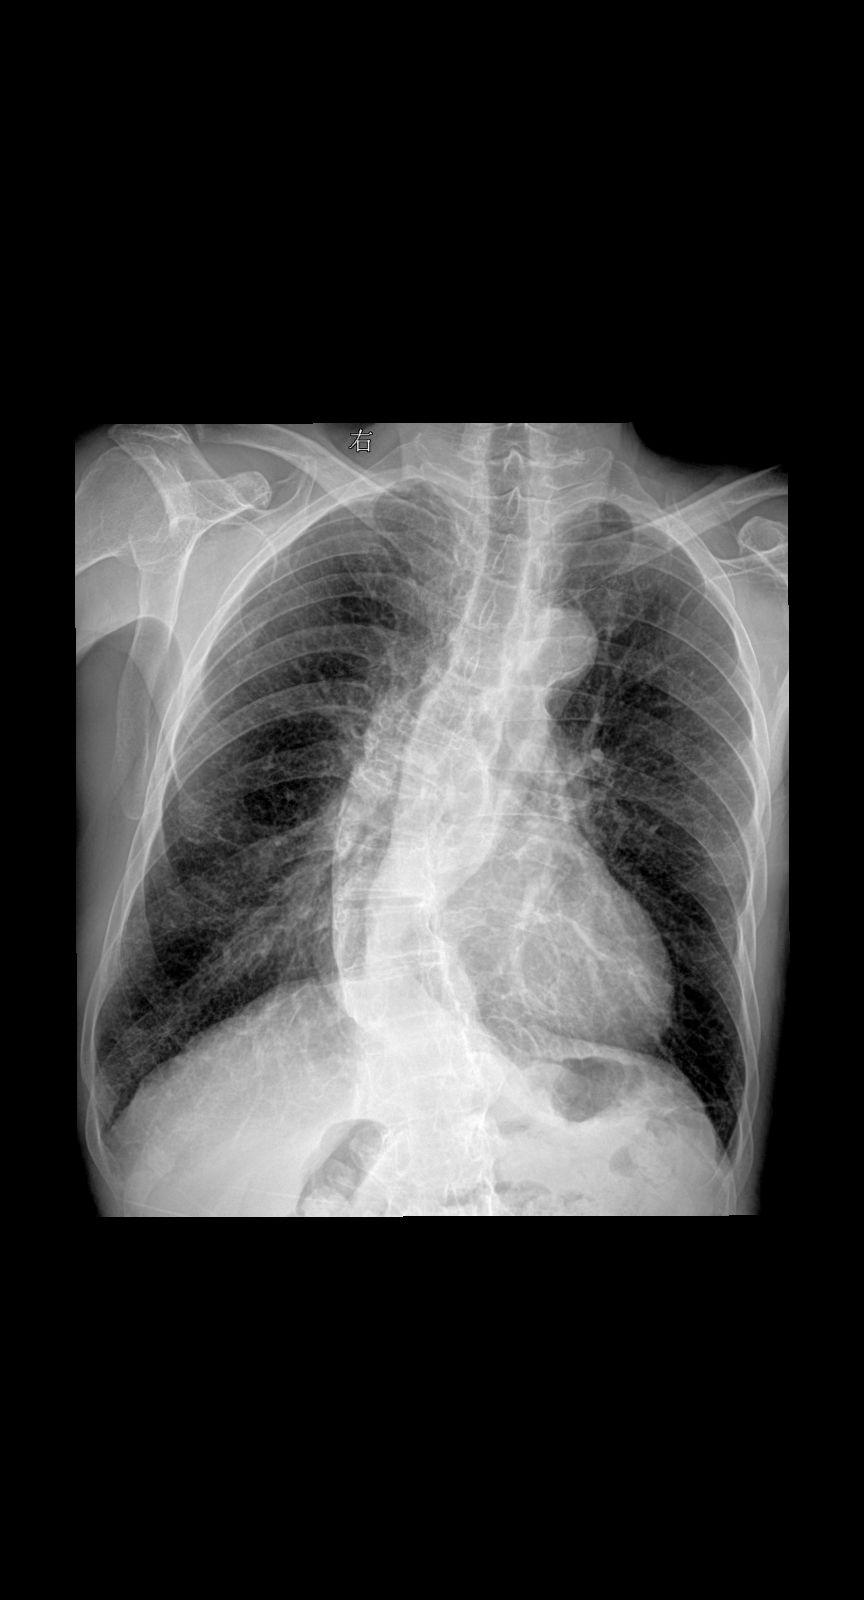

主诉:咳嗽 闷气 男 80y 考虑什么家人们?答案打到评论区

2025-02-25 16:12